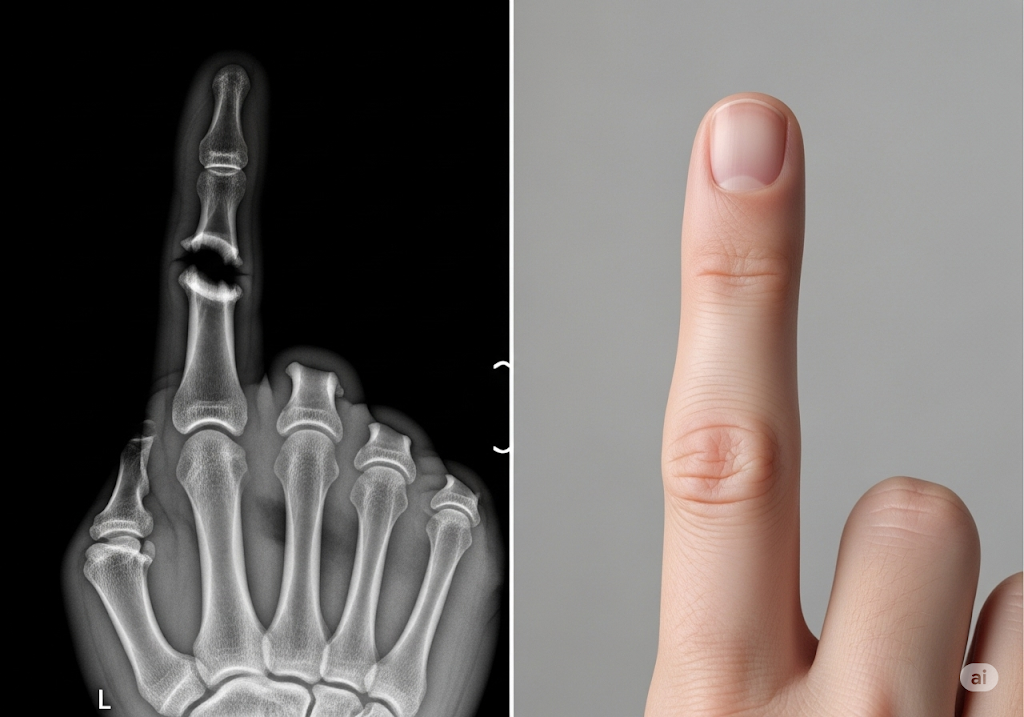

Научный подход компании базируется на применении протеина NELL-1, участвующего в физиологических процессах костеобразования. Лабораторные эксперименты зафиксировали уникальное свойство NELL-1 инициировать остеогенез исключительно в требуемых зонах, параллельно блокируя процессы адипогенеза.